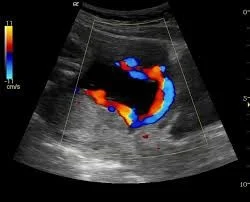

- During pregnancy by Doppler US

Occurs when fetal vessels traverse the fetal membranes over the internal cervical os.

Vasa Previa Diagnosis